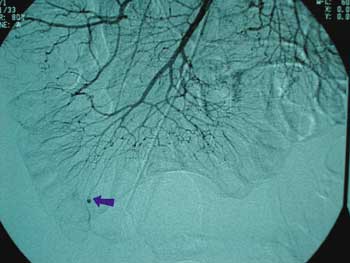

caráter de urgência, a arteriografia mesentérica, pela

provável origem jejuno-ileal do sangramento. Tal

exame demonstrou sangramento em atividade em

topografia do íleo terminal, proveniente de uma artéria

anômala, sendo a hipótese mais provável, um divertículo

de Meckel (Figura 1).

| Figura 1 _ Arteriografia mostrando sangramento em atividade em topografia do íleo terminal (seta). |

No caso em questão, a arteriografia

foi bastante sugestiva, o que nos permitiu incluir

como próximo passo, a realização de uma

videolaparoscopia, que inicialmente foi diagnóstica, com objetivo

de confirmar o achado arteriográfico. A confirmação